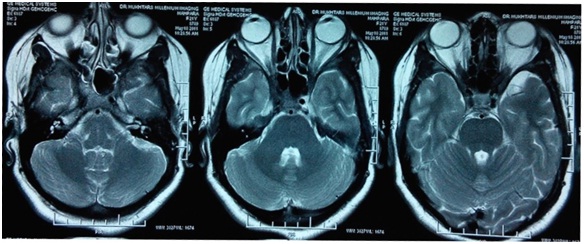

We present a 24 year old Asian female student presented with acute diminution of vision in both eyes 4 years back followed by complete loss of vision one year later in both eyes. There was no history of pain, redness in eyes, headache, blurring of vision, double vision, and inability to move eyeballs. Magnetic resonance imaging (MRI) of brain revealed normal study (Figure 1) and patient was started on intravenous methylprednisolone 1gram for three days followed by tapered dose of prednisolone but with no improvement in vision.

Figure 1- MRI Brain and Orbit showing normal study

Figure 2- MRI Brain and Orbit showing Normal Study